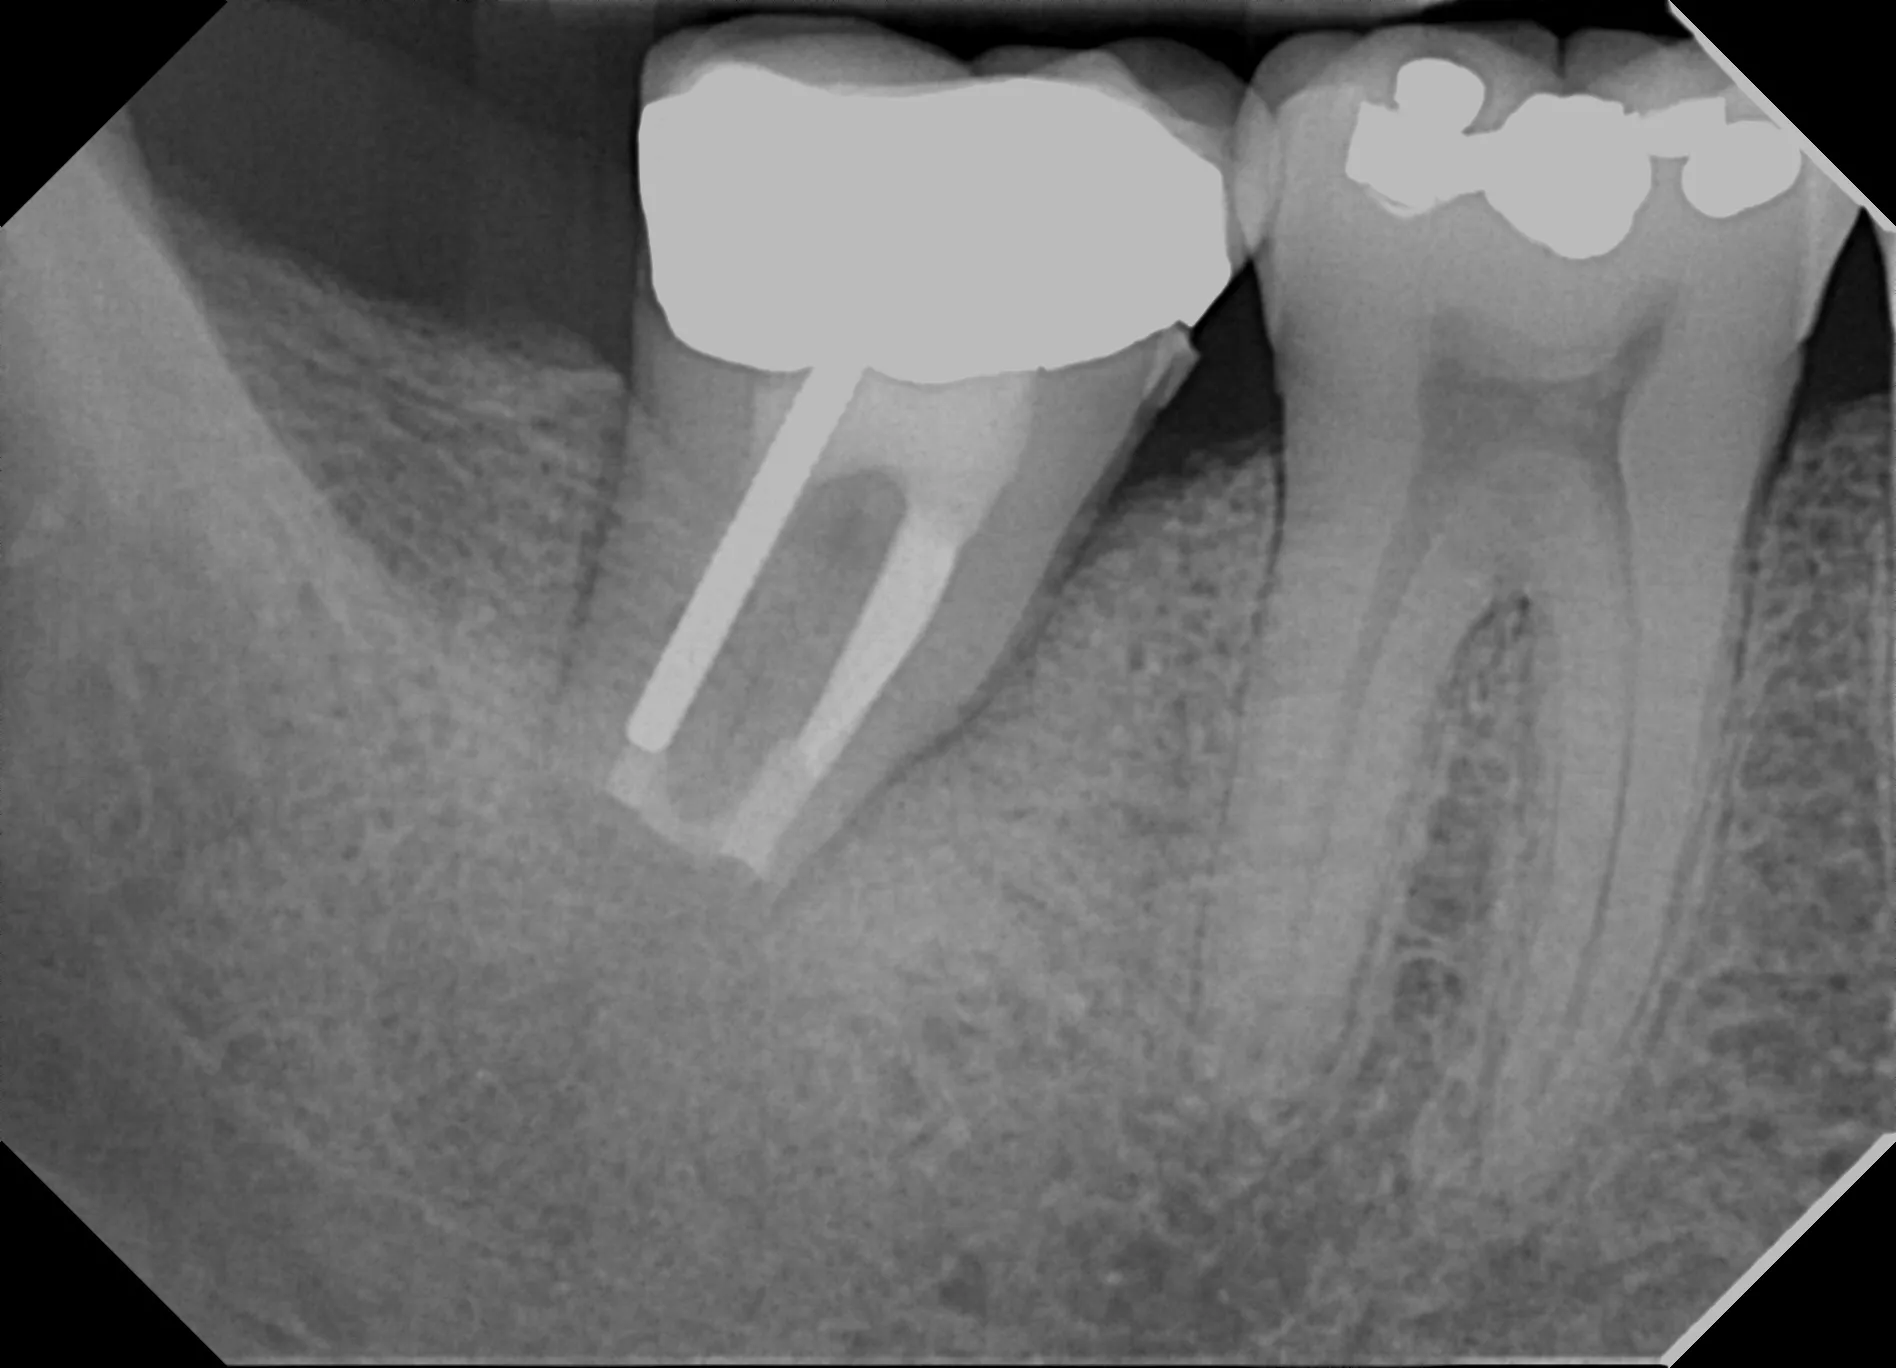

Atraumatic extraction with ultrasonic apical preparation and MTA retrofill, followed by immediate reimplantation

4. Retrograde Seal (Minutes 12-14):

• Place bioceramic material (MTA or EndoSequence Root Repair Material)

• Ensure complete seal of apical anatomy including isthmuses

• Verify material adaptation with magnification

5. Reimplantation (Minute 15):

• Irrigate socket with sterile saline immediately before reinsertion

• Gently seat tooth back into socket with firm digital pressure

• Verify positioning matches original position

• Check occlusion—tooth should not have premature contact

• Radiograph: Immediate postoperative film to document position

Patient Outcome in This Case

At 12-month recall:

• Complete resolution of pain and periapical symptoms

• Radiographic evidence of bone regeneration around apical region

• CBCT confirms healing of periapical lesion

• Tooth asymptomatic to percussion and palpation

• Normal function—patient reports no limitations

• No evidence of root resorption